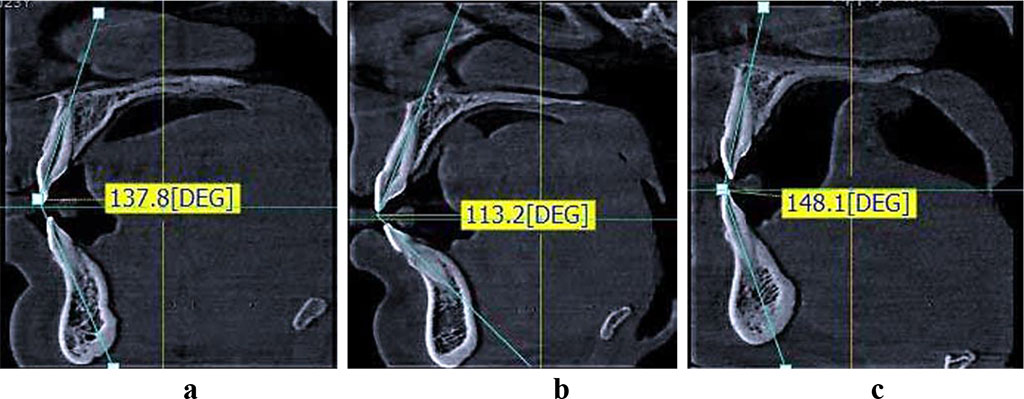

Stage

2 of the study involved 90 patients, and in view of the antagonizing

medial incisor angle, which reveals the trusive type of dental

arches, the patients were divided into three groups – Group 1

(n=33) were patients with the mesotrusive type of dental arches

(inter-incisal angle – 125°-140°); Group 2 (n=30) included

patients with the protrusive type of dental arches (inter-incisal

angle – below 125°), and Group 3 (n=27) were patients with the

retrusive type of dental arches (inter-incisal angle – above 140°)

(Fig. 3). All the patients had an optimal incisor overlap, both

vertical and horizontal.

Figure

3 – types of medial incisors location on the CBCT: a – patients

of Group 1 (mesotrusive dental arches); b – patients of Group 2

(protrusive dental arches); c - patients of Group 3 (retrusive dental

arches).